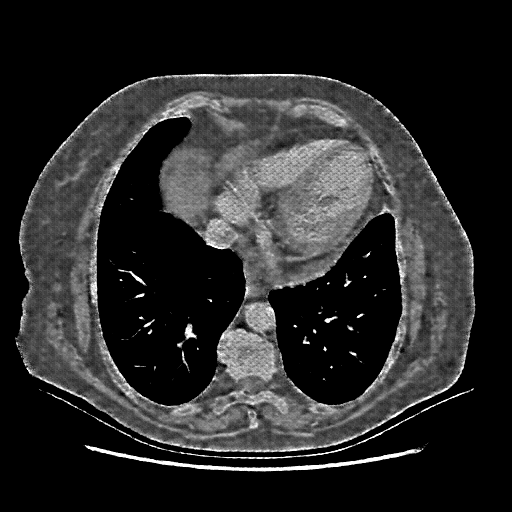

Targeted Slice 70 - Mediastinum Window Analysis (Generated vs Real Venous)

0.645

Mediastinum SSIM

47.0

Mediastinum RMSE

20.6

Mediastinum MAE

Average Mediastinum Window Metrics Across All Slices (101 slices) - Generated vs Real Venous

0.623

Mediastinum SSIM (Avg)

47.6

Mediastinum RMSE (Avg)

21.9

Mediastinum MAE (Avg)

Generated VENOUS CT scan (A→B translation)

Full window (WL 1023.5, WW 4095 β†’ Low βˆ’1024, High +3071)

Mediastinum window (WL 40, WW 400 β†’ Low βˆ’160, High +240)